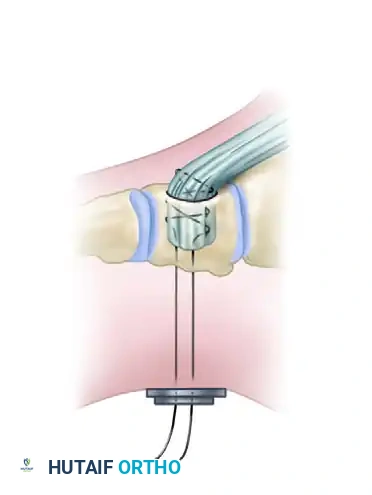

Detail of the osteotomy execution. Note the preservation of the plantar cortex to create a greenstick hinge.

Once all wedges are removed, apply gentle, sustained upward pressure on the plantar aspect of the metatarsal heads. The intact plantar cortices will undergo a controlled "greenstick" fracture, allowing the dorsal gaps to close flush.

Closure of the dorsal gaps. The greenstick fracture of the plantar cortex allows for elevation of the metatarsal heads, flattening the longitudinal arch.

If the cuts were precise and the plantar hinge is intact, the osteotomies are often inherently stable and may not require internal fixation. However, if instability is noted, or if the plantar cortex completely fractures, stabilization with crossed Kirschner wires (K-wires) or low-profile dorsal plates is mandatory.